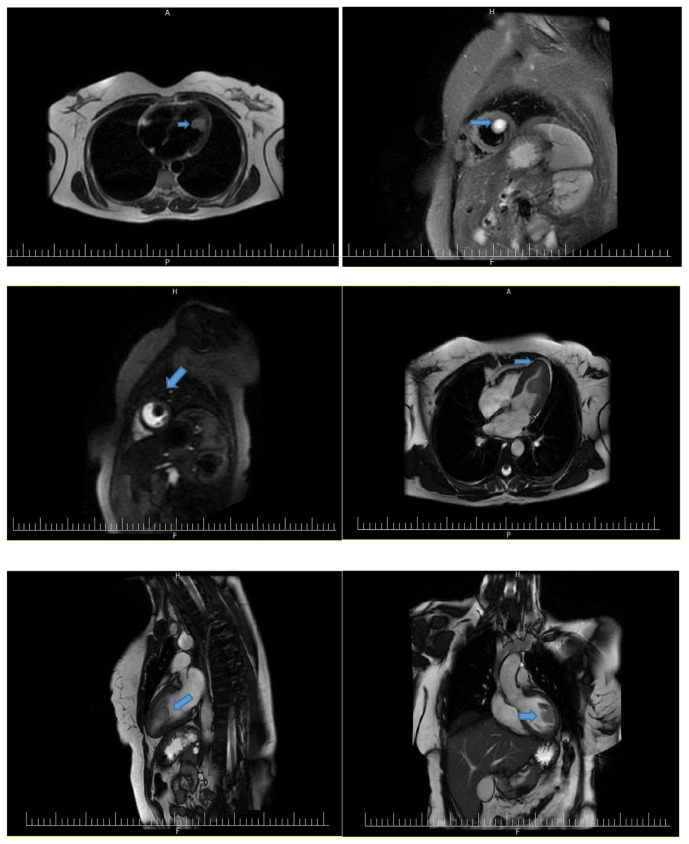

Case presentation: We present a case of a 46-year-old woman with positional vertigo and exertional dyspnea. Transthoracic echocardiography revealed a mobile oval-shaped mass in the left ventricle. Cardiac magnetic resonance imaging suggested a large papillary fibroelastoma. The tumor was successfully resected, and histopathological examination confirmed the diagnosis.

Conclusion: This case highlights the importance of thorough imaging and surgical intervention in managing large, nonvalvular PFEs, which, although rare, can lead to significant complications.